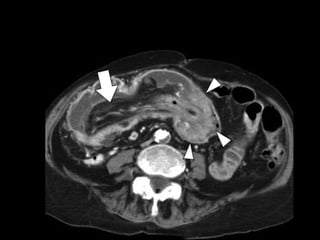

Colo-colic intussusception with a

leading point of adenocarcinoma

Colo-colic intussusception witha leading point of adenocarcinoma